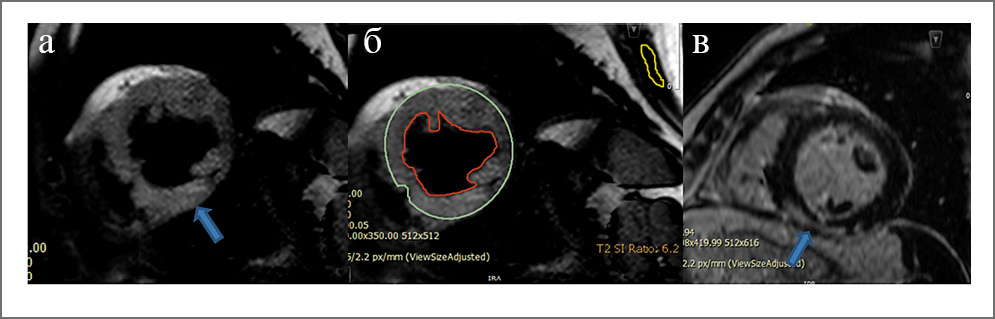

Рис. 2. МРТ пациента с острым миокардитом: а – изображения в режиме Т2 с жироподавлением, повышение МР-сигнала, соответствующее отеку (стрелка), в среднем нижнем сегменте миокарда ЛЖ; б – расчет соотношения интенсивности МР-сигнала от миокарда к интенсивности сигнала от скелетной мышцы (соотношение более 2 является критерием отека миокарда, Lake Louise); в – серия отсроченного контрастирования, интрамиокардиальное накопление контрастного препарата в среднем нижнем сегменте миокарда ЛЖ.